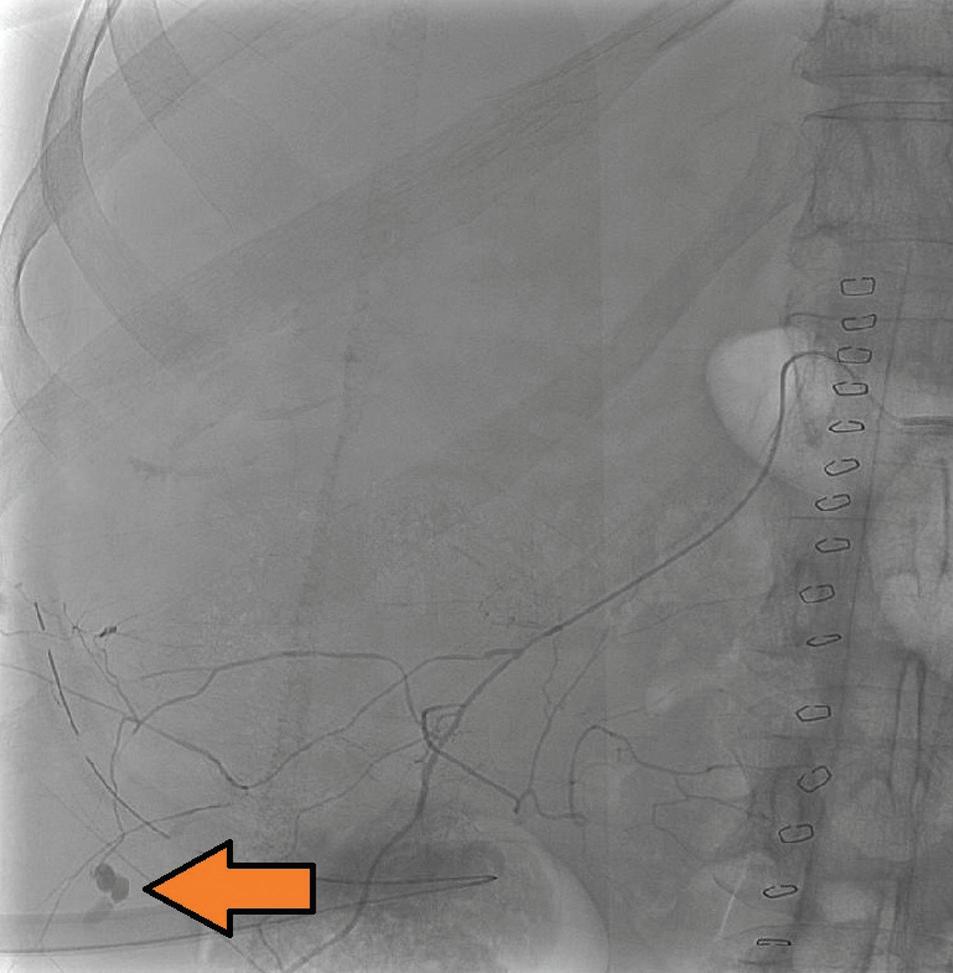

Vazografická obliterace krvácející arterie zádových svalů po bilaterální nefrektomii

Vasographic obliteration of a bleeding back muscle artery after bilateral nephrectomy of polycystic kidneys

Václav Krejčí, Miloš Broďák, Antonín Krajina, Jaroslav Pacovský

Celkem u 5 pac ie ntů v této skupině pak byl k dispozici kromě výsledku cytologie selektivní výplachové moči i výsledek cytologie moči spontánně vymočené. Jednalo se o 4 pacienty s HGUC a 1 pacienta s LGUC. Ve 2 případech (1 případ LGUC a 1 případ HGUC) dala jak výplachová, tak spontánní cytologie moči stejný negativní výsledek (NHGUC). Ve zbylých 3 případech se pak při různých typech odběru moči výsledky cytolog ie rozcházely. Ve 2 případech měla výplachová cytolog ie negativní výsledek, naopak cytologie spontánně vymočené moči byla klasifikována v kategorii SHGUC a HGUC. V 1 případě naopak výplachová cytologie dala atypický výsledek (AUC), cytologie spontánní moči byla negativní (NHGUC).

Skupina 3 – pacienti s močovou cytologií bez bližší specifikace typu odběru urologem

Do poslední skupiny bylo zařazeno celkem 18 pacientů. Jednalo se o případy, kdy na podkladě údajů uvedených na průvodce k cytologickému mater iálu nebylo možné zjistit, jaký způsob kolekce moči byl upřednostněn. V 8 případech se dle WHO 2022 jednalo o pacienty s biopticky verifikovaným LGUC, u 10 pacientů byl potvrzen HGUC. Dle WHO 1973 byli pacienti stratifikováni jako grade 1 ve 3 případech, grade 2 v 7 případech a grade 3 v 8 případech.

Dle Pařížské klasifikace bylo 8 případů kategorizováno jako NHGUC, 2 pacienti splnili kritér ia pro diagnózu AUC, 6 pacientů odpovídalo SHGUC a 2 pacienti byli z močové cytologie stratifikováni jako HGUC. Močová cytologie tak detekovala nádor u 10 z 18 pacientů, tj. souhrnná senzitivita cytolog ie moči pro záchyt UUTUC v této kategorii dosáhla 55 %. Močová cytologie odhalila 7 HGUC (70 %) a 3 LGUC (38 %).

Diskuze

Močová cytologie má relativně vysokou senzitivitu pro detekci HGUC, naopak senzitivita detekce LGUC je nízká a vykazuje značnou interobservační variabilitu [10]. V roce 2016 publikovaná Pařížská klasifikace pro reportování močové cytologie si kladla za cíl jasnou standardizaci jednotlivých cytologických d ia gnostických kritér ií a sjednocení reportování pro přesnější stratifikaci pacientů a jejich následný lepší klinický management [6]. Klasifikace byla velmi dobře přijata odbornou veřejností, což vedlo k její rychlé inkorporaci do rutinní cytologické praxe a diagnostiky [11]. V roce 2021 vyšlo druhé editované vydání klasifikace, které však v porovnání s původní verzí přineslo jen minimální změny [12]. Pařížská klasifikace pro reportování močové cytologie se postavila čelem k nejčastějším a nejvýraznějším úskalím dřívějších klasifikací močové cytologie – zejména se „přiznala“ k limitacím močové cytologie při záchytu LG uroteliálních lézí (uroteliální papilom, papilární uroteliální neoplazie nízkého maligního potenciálu a LGUC) a začala se orientovat preferenčně na záchyt HGUC. Tomu přizpůsobila i název „benigní/negativní“ kategor ie, která od roku 2016 nese název „negativní pro HGUC“. Dále Pařížská klasifikace jasným vytyčením diagnostických kritérií pro jednotlivé diagnostické kategorie napomáhá přesnější stratifikaci nálezů, snižuje interobservační variabilitu při hodnocení a snižuje též počet vzorků hodnocených jako „atypické“ [9,13], tedy v kategorii, která dříve sloužila jako pomyslný odpadkový koš méně jasných případů. I přes jasné nastavení Pařížské klasifikace, soustředící se na záchyt HGUC a spíše „ignorující“ LG léze, dále přetrvávají snahy některých autorů o přesnější cytologickou diagnostiku LG lézí. V literatuře tak lze dohledat popisy určitého spektra různě diskrétních atypií, které mohou být s cytologickým záchytem LG uroteliální léze asociované. Autoři však sami přiznávají, že využití těchto poznatků v rutinní praxi je limitované [14].

Je nutné si uvědomit, že výsledek/nález v močové cytologii je výrazně ovlivněn zvoleným způsobem odběru vzorku moči. V praxi lze odebírat a cytologicky vyšetřovat dva hlavní typy moči – moč vymočenou spontánně a moč získanou instrumentací močových cest (tj. moč výplachovou, moč získanou vymočením bezprostředně po invazivním výkonu na močových cestách či moč získanou z močového katetru). Raab et al. ukázali, že vzorky spontánně vymočené moči by měly vykazovat vyšší specificitu a lehce nižší senzitivitu než instrumentálně získaný vzorek [15]. Výplachový odběr/instrumentace sice resultuje ve vzorek s vyšší celularitou a lepší prezervací buněk, instrumentace však generuje artefakty, které dle některých studií vedou k falešně pozitivnímu výsledku (atypický/suspektní výsledek) vyšetření až v 15,6 % případů [16]. Proto je důležité uvádět způsob, jakým byl vzorek moči odebrán, na průvodní list k cytologickému materiálu. Informace o typu odběru je pro objektivní posouzení vzorku patologem absolutní nutností. Typ odběru moči se výrazně promítá do

cytologických znaků zastižených ve vzorku, které mohou být při neznalosti typu odběru obtížně interpretovatelné.

Močová cytologie je některými pracovišti využívána při záchytu UC zejména dolních močových cest (v rámci primodiagnostiky, ale i k dispenzarizaci pacientů), většinou však pouze jen jako doplňková metoda. V rámci dolních močových cest je senzitivita močové cytologie při detekci HGUC v literatuře uváděna v rozmezí 40–84 % při specificitě 73–100 % [8,17,18].

Zlatým standardem pro d ia gnostiku UC je však invazivní vyšetření (cystoskop ie ) a odběr b io ps ie. Atraktivita možného širšího využití cytologie moči tkví v neinvazivitě vyšetření a menší finanční náročnosti (tyto výhody pochopitelně odpadají v případě provedení výplachové cytologie při cystoskopii).

Zkušenosti s využitím močové cytologie při detekci UUTUC (jak literární, tak i z rutinní praxe) nejsou při nižším výskytu tumorů horních cest močových většinou příliš rozsáhlé. Některá literární data však poukazují na nižší senzitivitu močové cytologie pro detekci HGUC v horních močových cestách oproti UC močového měchýře [8,19]. Na vině může být fakt, že při cytologické detekci UUTUC js ou urotelie (benigní i neoplastické) během putování z pánvičky/ureteru vystavené relativně hostilnímu působení moči po delší dobu. Navíc se na jejich prezervaci negativně podepisuje také mechanické působení ureterální peristaltiky. Senzitivita močové cytolog ie pro záchyt UUTUC je tak v různých studiích uváděna v širokém rozmezí od 43 do 92 % [2,17–22]. Autoři Potretzke et al. provedli statistický souhrn a metaanalýzu prací zabývajících se specificky selektivní výplachovou cytologií při screeningu UUTUC a uvádějí, že průměrná senzitivita záchytu UUTUC z močové cytologie (při korelaci s finální bioptickou diagnózou) u selektivních výplachových vzorků dosahuje 53 % (při celkovém rozmezí 21–77 %) [20].

V literatuře bývá diskutovaná problematika volby nejvhodnější metody odběru moči pro cytologické vyšetření při detekci UUTUC, výsledky jsou relativně konfliktní a lze dohledat práce preferující instrumentální (výplachový) odběr i moč spontánně vymočen ou. Stud ie ně kte rých kolektivů tak ukazují, že cytologické vyšetření provedené z výplachového vzorku má v případě UUTUC lepší výtěžnost než cytologie spontánně vymočené moči [19,23–25]. Konkrétně autoři Zhang et al. ve své práci porovnávali senzitivitu výplachové a spontánní cytologie u retrospektivně vyhledaných HG UUTUC. V případě spontánních vzorků moči byla senzitiva záchytu HGUC 27 %, při započtení i atypických kategorií do celkového výsledku pak senzitivita dosáhla až 83 %. U výplachových vzorků byl HGUC správně detekován v 62,5 % případů, při započítání atypicky hodnocených případů až u 100 % [2]. Zheng et al. ve své studii zabývající se diagnostikou UUTUC ze selektivní výplachové cytologie popsali senzitivu a specificitu detekce HGUC 78, resp. 91 % (při započtení SHGUC a HGUC kategorie) [26]. V práci autorů Simon et al. senzitivita

Ces Urol 2025; 29(1): 22– 28

cytologického vyšetření při detekci HGUC ze selektivních výplachových vzorků dosahovala 19 %, při započtení cytologických kategorií SHGUC a AUC potom až 85 % [23]. Kolektiv autorů v čele s McIntire ve své práci reportuje 82% senzitivitu při detekci HGUC z výplachových vzorků [9]. Chen et al. při hodnocení výplachových vzorků dosáhli při detekci HG UUTUC senzitivity a specificity 71,4, resp. 91,9 % a senzitivity/specificity při detekci LG UUTUC 21,4, resp. 100 % (při započítání pozitivních a atypických diagnóz) [25]. V literatuře jsou však k dohledání i práce, které přínos selektivních výplachových cytologií spíše zpochybňují. Například autoři Dev et al. ve své práci zahrnující 100 pacientů s UUTUC porovnávali výsledky spontánní a selektivní výplachové cytolog ie a došli k závěru, že výplachová cytologie přináší oproti spontánně vymočené moči p ouze zcela marginálně zvýšen ou senzitivitu záchytu [27].

V našem souboru senzitivita močové cytologie při detekci HG UUTUC činila 65, resp. 55 % (spontánní moč vs. instrumentální odběr/selektivní výplach). U pacientů, u nichž způsob odběru moči nebyl urologem specifikován, byla senzitivita cytologie moči pro záchyt HG UUTUC 70 %. Průměrná senzitivita všech tří skupin byla při detekci HG UUTUC stanovena na 64 %. Stejný fenomén pak pozorujeme i v rámci hodnocení senzitivity močové cytologie při detekci LG UUTUC, kdy spontánní moč přinesla senzitivitu 40 %, selektivní výplach 20 % a u pacientů s blíže nespecifikovaným způsobem kolekce moči 38 %. Celková senzitivita močové cytologie pro detekci LG UUTUC odpovídala 36 %. Naše výsledky hovoří ve prospěch spontánních vzorků při detekci LG i HG UUTUC. Relativně nejvyšší senzitivitu močové cytologie u pacientů bez informace o způsobu kolekce moči (skupina 3) lze jen obtížně vysvětlit. Čistě hypoteticky, pokud patolog postrádá základní informace o typu odběru na průvodním listu k cytologickému materiálu, lze počítat s tím, že při diagnostice ke vzorku přistupuje agresivněji (počítá vždy s horší variantou). Je však třeba si uvědomit, že v rámci této studie bylo pracováno pouze s pacienty s finálně verifikovaným UUTUC. Velmi zajímavé by mohlo být statistické zhodnocení falešné pozitivity močové cytologie u pacientů, u nichž následnou biopsií nebyla přítomnost UC prokázána (a zejména pak u pacientů bez specifikace typu odběru moči). Toto hodnocení však není cílem a součástí zde předkládané práce.

Mezi limity naší práce patří retrospektivní charakter studie, malá velikost kohorty (ostatně stejně jako i u většiny podobných dostupných prací, kdy vzácnost výskytu UUTUC nedovoluje vytvořit větší soubor). Další limitací modifikující výsledky studie je i výše komentovaný výrazný selekční bias (využití výsledků močové cytologie jen u pacientů s histologicky prokázaným UUTUC, a nikoliv u všech pacientů s podezřením na UUTUC na základě zobrazovacích metod), kdy při absenci nenádorové kontrolní skupiny lze počítat s nadhodnocením zjištěné senzitivity. Neméně významným faktem ovlivňujícím výsledky studie je i neznalost typu kolekce moči u signifikantní části pacientů (26 %) zařazených do této studie. S podobnými limity se však setkává většina v literatuře dostupných prací. Velké množství proměnných v různých originálních studiích nedovoluje provést jednoduché „head to head“ porovnání výsledků. Jednoznačná odpověď na otázku, který typ kolekce močové cytologie je při detekci UUTUC nejlepší, tak v s ou časné době neexistuje. Jako nejslibnější způsob, jak najít odpověď na tuto otázku, se jeví standardizovaná prospektivní studie s jasně nastavenými inkluzními kritérii, odběrem vzorků, termínovými omezeními a jasně danými diagnostickými algoritmy.

Závěr

Senzitivita močové cytologie pro záchyt UUTUC (bez ohledu na definitivní LG či HG histologickou diagnózu) činila ve skupině se spontánním odběrem moči 50 %, ve skupině pacientů se selektivním výplachem 44 % a ve skupině bez specifikace odběru 55 %. Močová cytologie správně detekovala celkem 64 % HG UUTUC, u LG UUTUC cytologie odhalila tumor v 36 % případů. Senzitivita močové cytologie pro záchyt UUTUC je tak porovnatelná s dostupnými literárními daty pro záchyt UC dolních močových cest a s močovou cytologií obecně, pohybuje se však spíše při dolní hranici v literatuře uváděného rozmezí senzitivity pro močovou cytologii dolních močových cest. Naše výsledky hovoří relativně ve prospěch spontánního odběru moči při detekci UUTUC.

Střet zájmů: Autoři prohlašují, že nemají žádný konflikt zájmů.

Prohlášení o podpoře: Karlova Univerzita Praha, Lékařská fakulta Plzeň (Cooperatio Program, SURG), Institucionální výzkum Fakultní nemocnice Plzeň (FNPl 00669806).

Literatura

1. Williamson SR, McKenney JK, Raspollini MR et al. Invasive urothelial carcinoma. In: WHO Classification of Tumours Editorial Board. Urinary and male genital tumours. Lyon (France): International Agency for Research on Cancer. 5th ed, 2022.

2. Zhang ML, Rosenthal DL, VandenBussche CJ. Upper urinary tract washings outperform voided urine specimens to detect upper tract high-grade urothelial carcinoma. Diagn Cytopathol 2017; 45(8): 700– 704. doi: 10.1002/ dc.23746.

3. Bagley DH, Huffman JL, Lyon ES. Flexible ureteropyeloscopy: diagnosis and treatment in the upper urinary tract. J Urol 1987; 138(2): 280– 285. doi: 10.1016/ s0022-5347(17)43119-3.

4. Pivovarcikova K, Pitra T, Alaghehbandan R et al. Lynch syndrome-associated upper tract urothelial carcinoma frequently occurs in patients older than 60 years: an opportunity to revisit urology clinical guidelines. Virchows Arch 2023; 483(4): 517– 526. doi: 10.1007/ s00428-023-03626-2.

5. Pitra T, Pivovarčíková K, Sedláčková H et al. Lynchův syndrom v rukách urologa. Ces Urol 2017; 21(4): 272– 279. doi: 10.48095/ cccu2017045.

6. Rouprêt M, Babjuk M, Burger M et al. European Association of Urology Guidelines on upper urinary tract urothelial carcinoma: 2020 update. Eur Urol 2021; 79(1): 62– 79. doi: 10.1016/ j.eururo.2020.05.042.